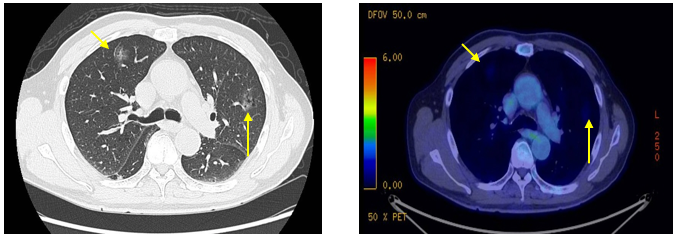

PET-CT(2023年9月):右下肺叶发现6.9×6.7×6.6cm的FDG高摄取肿块,伴右侧第7、8肋骨侵犯可疑,右肺门淋巴结肿大,双肺上叶多发结节,考虑腺癌谱系疾病。

CT及PET-CT随访(2023年11月、2024年1月):评估新辅助治疗效果,右下肺叶肿块缩小,右肺门淋巴结代谢活性消失,右肺上叶结节稳定但代谢活性降低,左肺上叶及双侧磨玻璃样病变稳定。